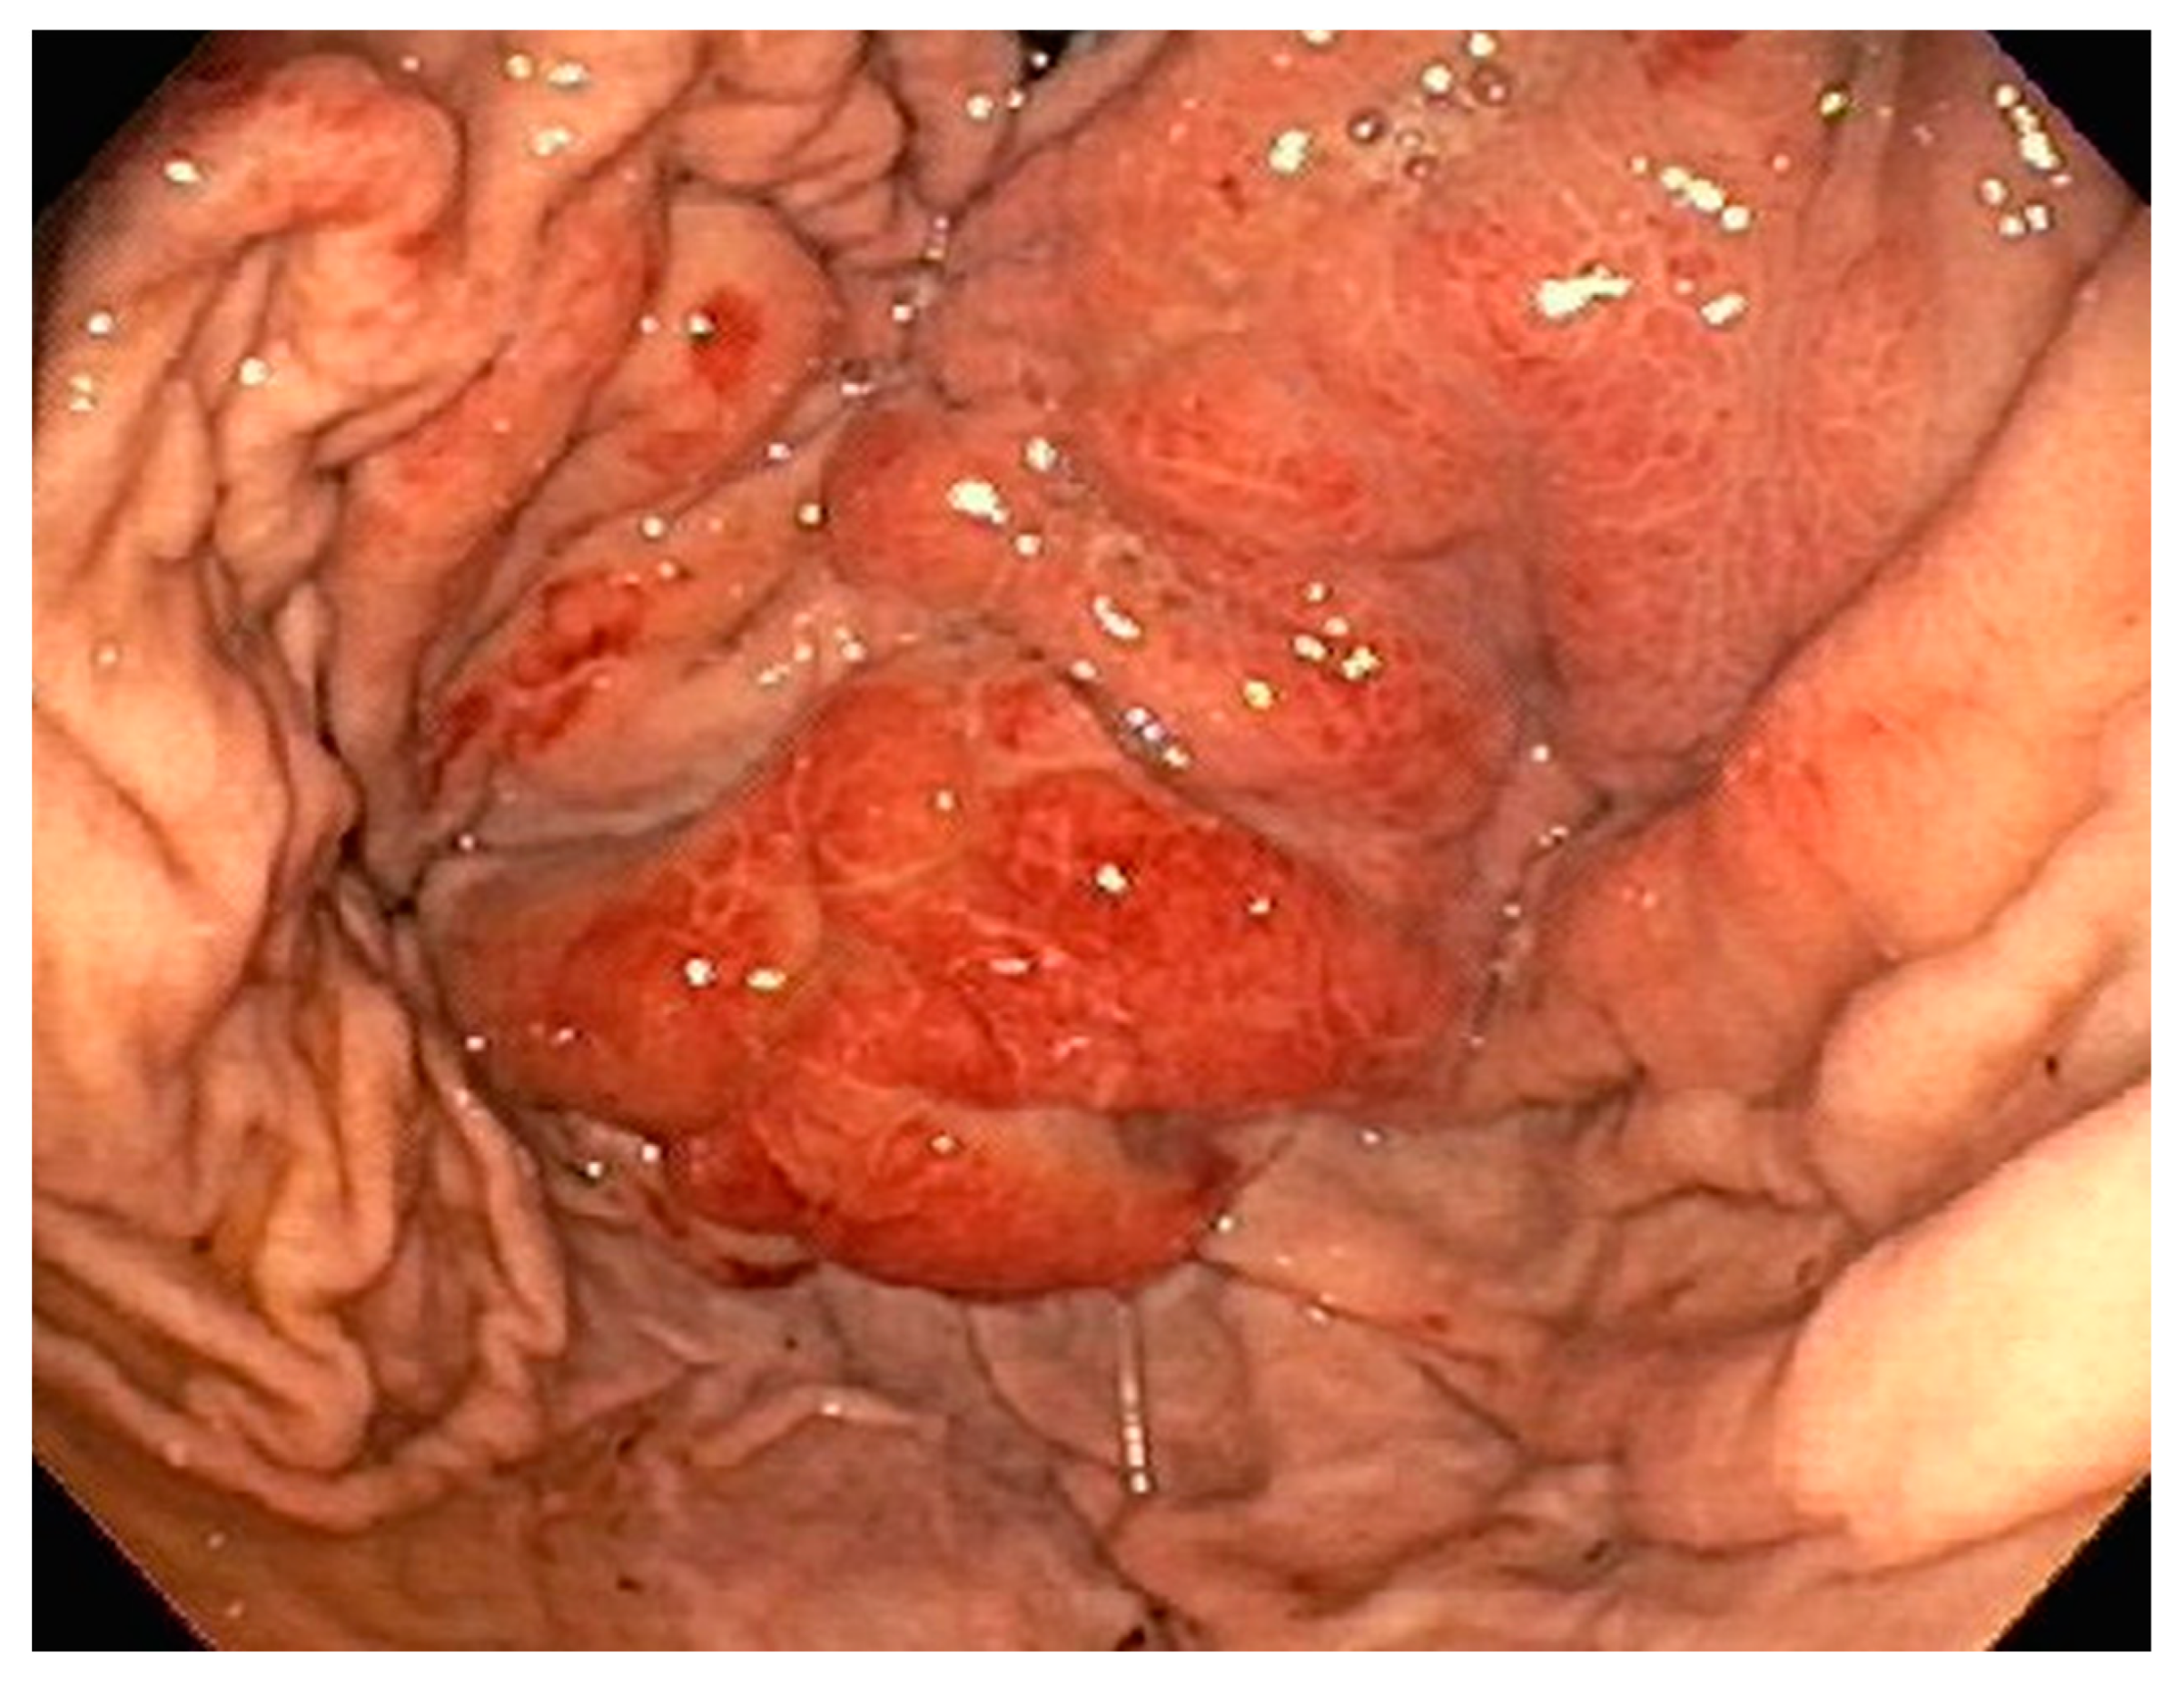

| 1 | F | 66 | Skin | Fundus, cardia, and body | Polypoid lesions with superficial ulcers | Esophagus, duodenum, mediastinum, cervical soft tissue, pancreas | Metastatic malignant melanoma | Radiotherapy and immunotherapy | Comfort care and death 5 days after EGD diagnosis of metastasis |

| 3 | F | 35 | Lung | Fundus | Fungating mass | Esophagus, mediastinum | Large-cell neuroendocrine carcinoma | Chemotherapy-carboplatin/ etoposide | Death 1 month after EGD diagnosis of metastasis |

| 4 | F | 73 | Kidney | Fundus and body | Multiple large friable masses | Liver and lungs | Clear cell renal carcinoma | Nephrectomy, chemotherapy, immunotherapy (Axitinib) | Death 10 days after EGD diagnosis of metastasis |